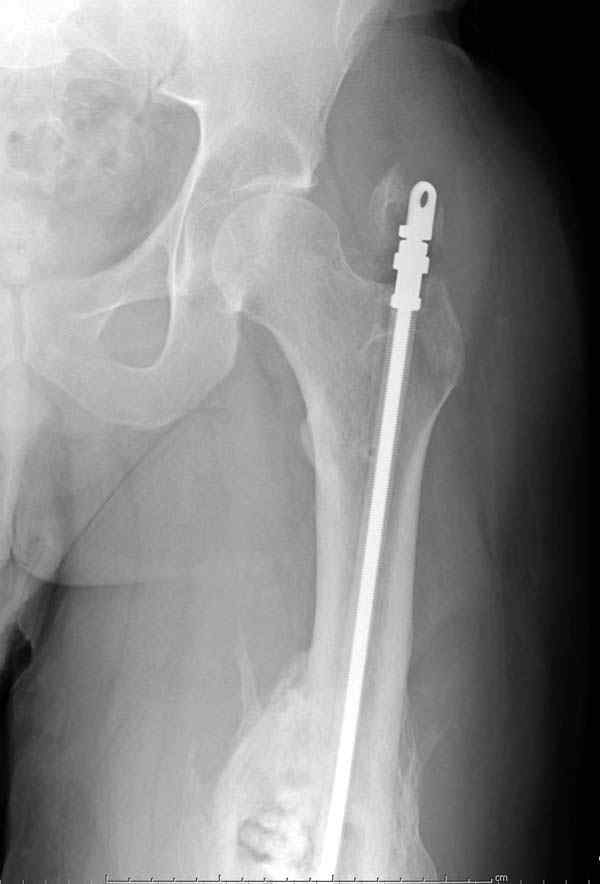

Через 4,5 лет после травмы выявлены рентгенологические признаки консолидации перелома, признаки хронического остеомиелита купировались. Аппарат был демонтирован. Пациент продолжил ходьбу с дозированной нагрузкой на конечность при помощи костылей. Через 2 месяца начал ходить при помощи трости. Однако, еще через 2 месяца отметил появление свищей на бедре с гнойным отделяемым и укорочение длины конечности. При осмотре в январе 2007 г.: пациент ходит при помощи костылей без опоры на левую нижнюю конечность, на бедре имеются множественные рубцы, на наружной поверхности сегмента в верхней и нижней третях имеются два свищевых хода со скудным серозно-гнойным отделяемым; отечности тканей конечности нет, пальпация безболезненная, отмечается укорочение длины конечности на 5 см, патологическая подвижность не определяется, имеется стойкая разгибательная контрактура коленного сустава (разгибание - 180 гр, сгибание - 170 гр), признаков нарушения кровоснабжения и иннервации тканей конечности нет. Температура тела нормальная. В общих анализах крови и мочи отклонений от нормы нет. [image 06,07, 08 (стрелками отмечены свищевые раны, 09, 10]Дорогие коллеги, я уверен, что у многих из вас после знакомства с данным клиническим наблюдением появится множество вопросов, касающихся уже проведенного лечения (особенно, сроков и способов). Сразу оговорюсь - я не смогу правильно ответить на многие вопросы (особенно касающиеся предшествующего периода лечения). Прошу вас, конечно по возможности, сосредоточить внимание не на разборе допущенных ошибок (проведенного лечения), а помочь добрым советом относительно тактики наших дальнейших действий. Наверное, кто-то располагает бесценным опытом лечения подобной патологии.